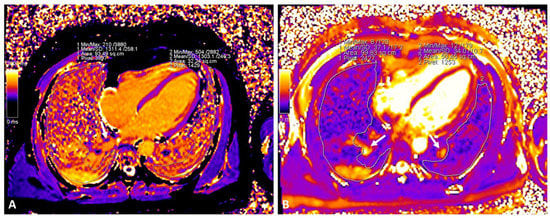

| Lung T1 mapping | |||

| Global | 1278 (1238, 1313) | 1149 (1107, 1249) | 0.003 |

| Remote | 1238 (1165, 1337) | 1152 (1114, 1249) | 0.088 |

| Affected | 1375 (1220, 1580) | 1201 (1130, 1270) | 0.016 |

| Lung T2 mapping | |||

| Global | 38 (36, 49) | 34 (28,39) | 0.040 |

| Remote | 29 (27, 35) | 33 (27, 41) | 0.797 |

| Affected | 70 (55, 82) | 30 (28, 40) | 0.001 |